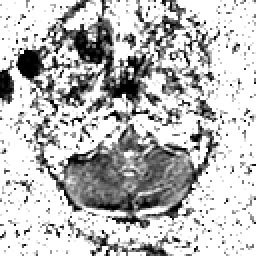

Alzheimer's Disease: SPECT/fMRI overlay -- Slice #0

Click on sagittal image to select slice. Click on thin tickmark to change timepoint, or thick tickmark for overlay.

Keith A. Johnson (keith@bwh.harvard.edu), J. Alex Becker (jabecker@mit.edu)